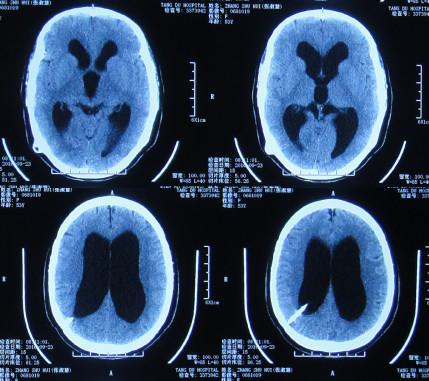

当天头颅CT:脑积水右侧侧脑室分流术后,脑室扩张并间质性脑水肿(图-12)。

图-12:2016年10月7日头颅CT

住院第2天即2016年10月8日,进行了原侧脑室脑脊液分流管去除术+右侧侧脑室外引流术,术后当天复查头颅CT:脑室引流术后状态(图-13)。

图-13:2016年10月8日头颅CT

引流术后第5天即2016年10月13日,复查头颅CT:右侧脑室较入院时缩小(图-16)

图-16:2016年10月13日头颅CT

第2次术后40天即2016年12月3日,头颅CT:脑室较入院时明显缩小(图-20)。

图-20:CT 对比图